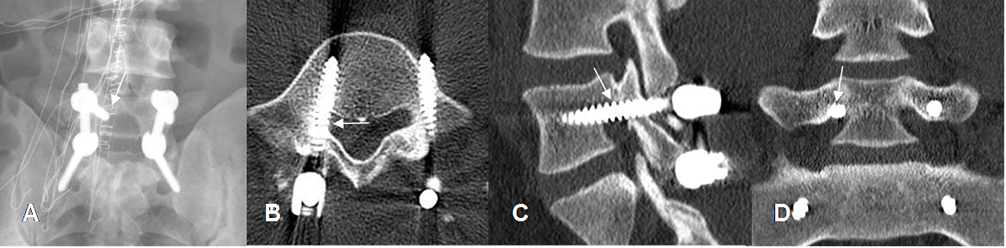

Fig 136. Mal posición de tornillos.

A: Rx AP. Tornillo superior derecho, con extremo medializado. (Flecha).

B: TAC axial. El tornillo derecho rompe la cortical medial y ocupa el receso lateral. (Flecha). El izquierdo, rompe la cortical anterior de la vértebra.

C: TAC reconstrucción sagital y D: TAC reconstrucción coronal. El tornillo ocupa la parte superior del agujero de conjunción, lugar por donde sale la raíz nerviosa. (Flechas).